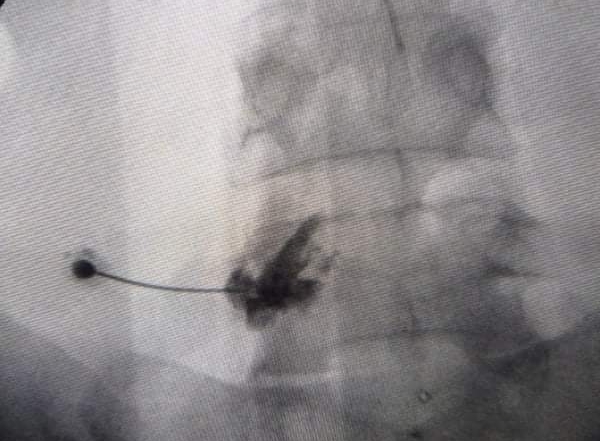

الصحة: “الحقن التداخلي ” برتوكول علاجي جديد يسجل نجاحات مميزة بمجمع الشفاء الطبي